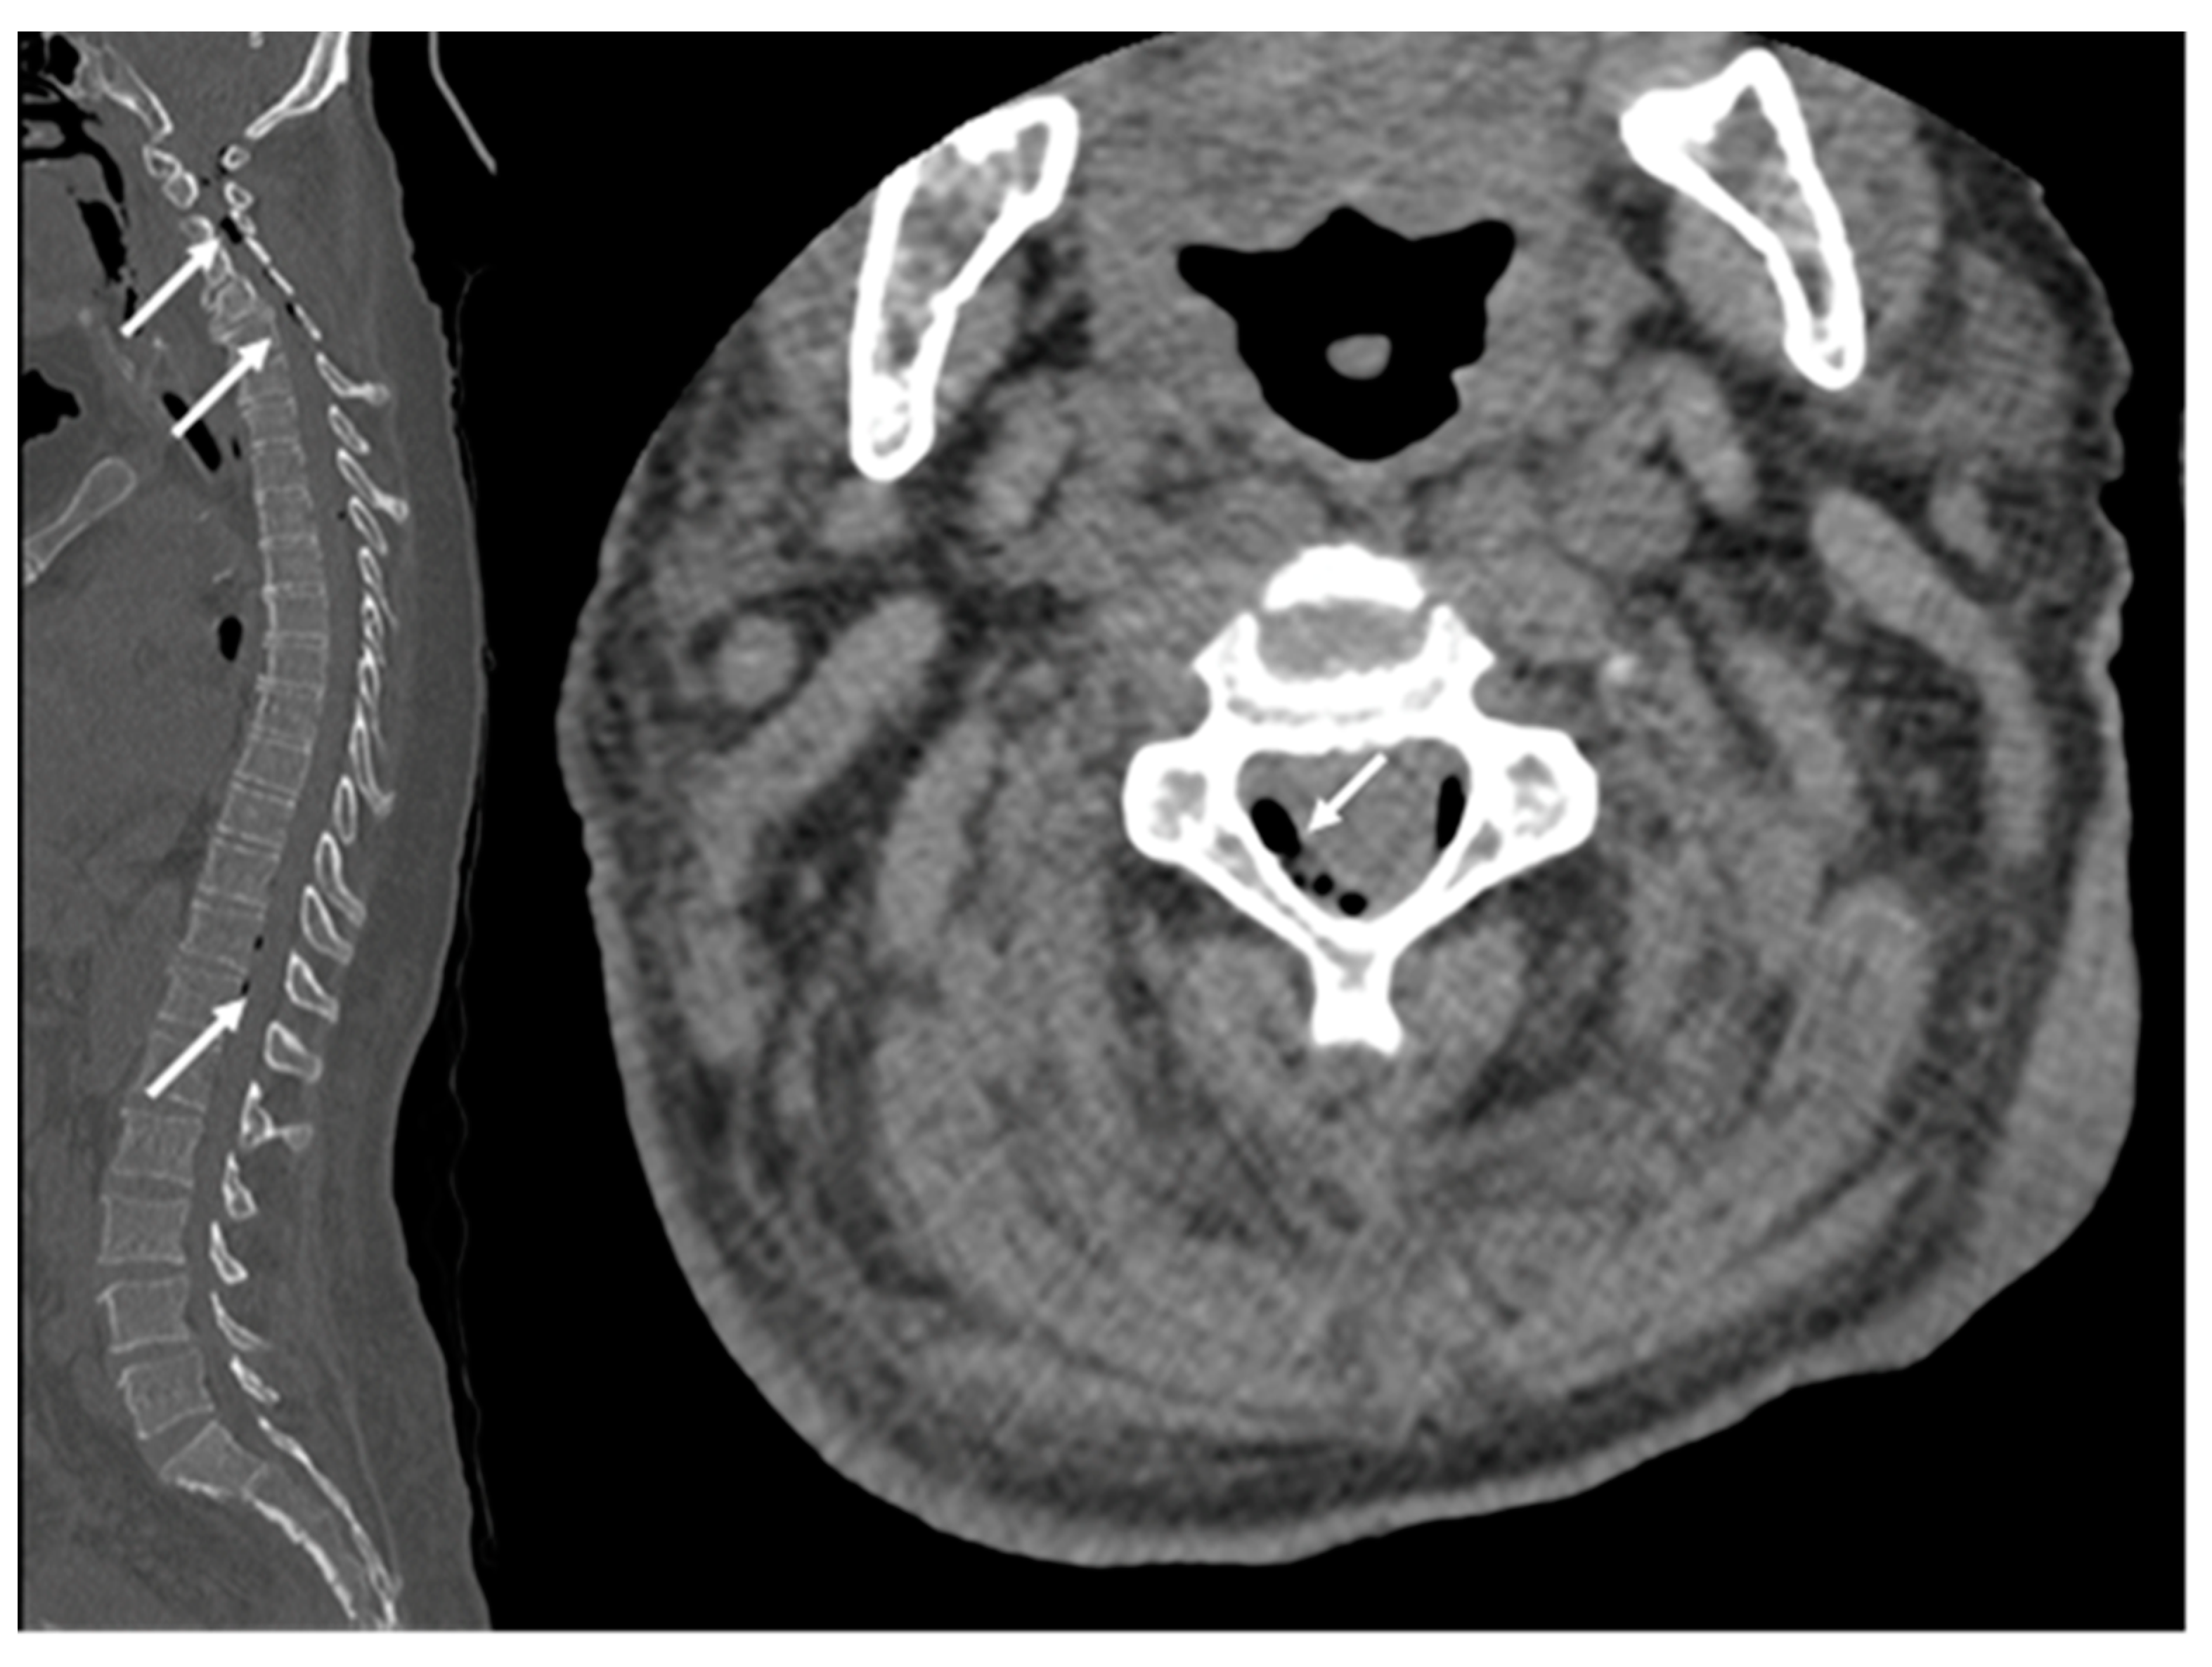

2.1. Case Report